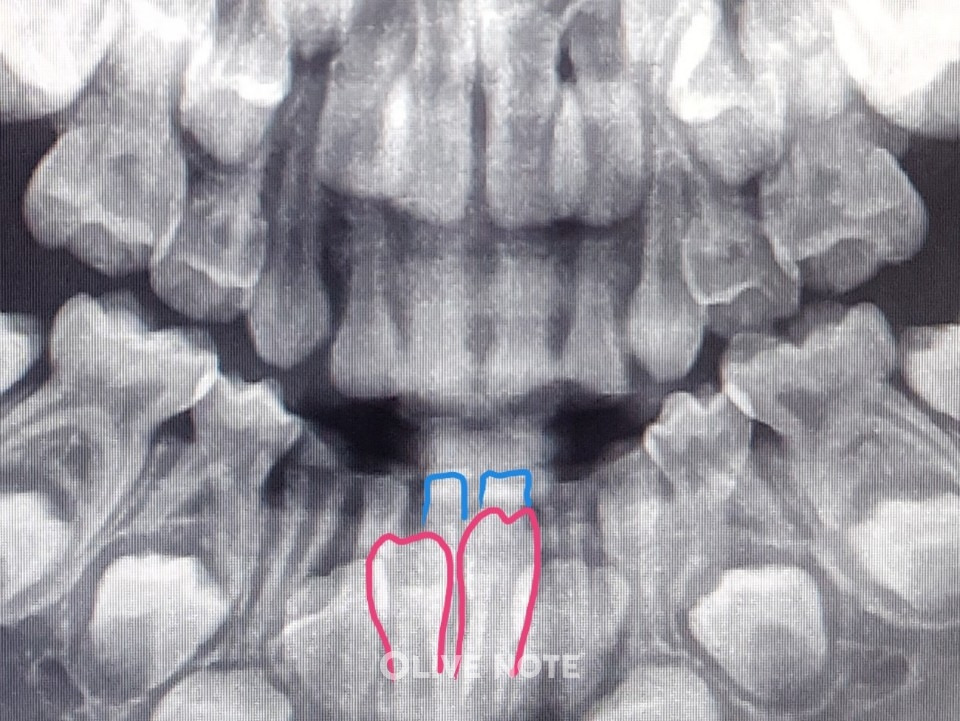

3140_8153_237.jpg 엑스레이를 찍어 영구치(빨간색)가 충분히 올라 왔다는 게 확인되면 유치(파란색)를 뽑아요.

Q. 이가 흔들리는 걸 확인한 후 치과에 가면 바로 발치할 수 있나요?

A. 아닙니다. 이가 흔들린다고 무조건 발치하지 않습니다. 치아 엑스레이를 찍어 영구치가 충분히 올라왔는지 확인해야 합니다. 너무 일찍 유치를 빼면 옆의 이가 기울어질 수 있고 밥을 먹을 때 불편하기 때문이죠.